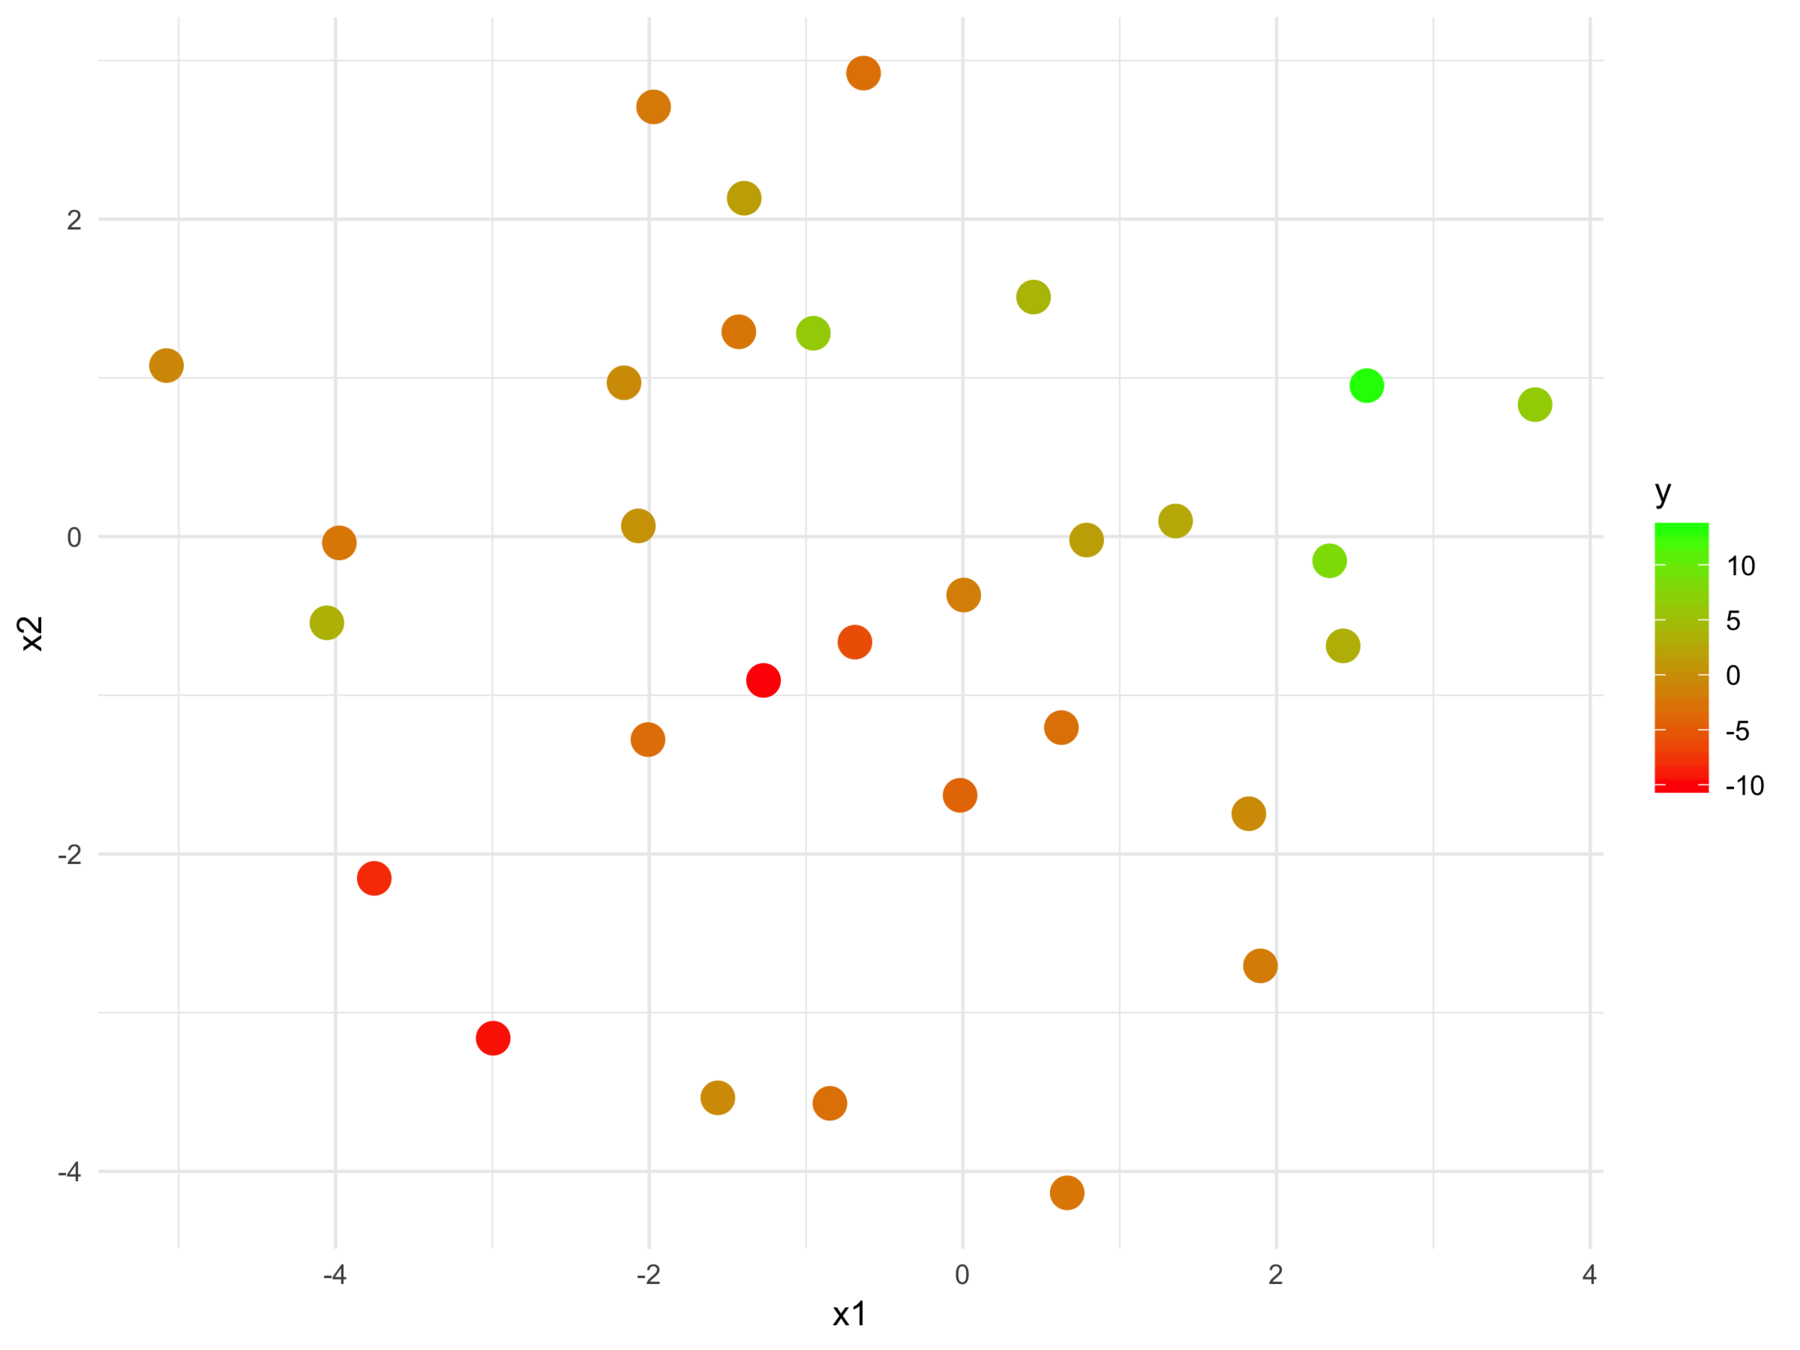

F-statistic: 24.7 on 2 and 28 DF, p-value: 6.572e-07We can't tell this

from this

The model fits relationships between the regressors and the outcome

But we may want the relationships between the regressors with respect to the outcome